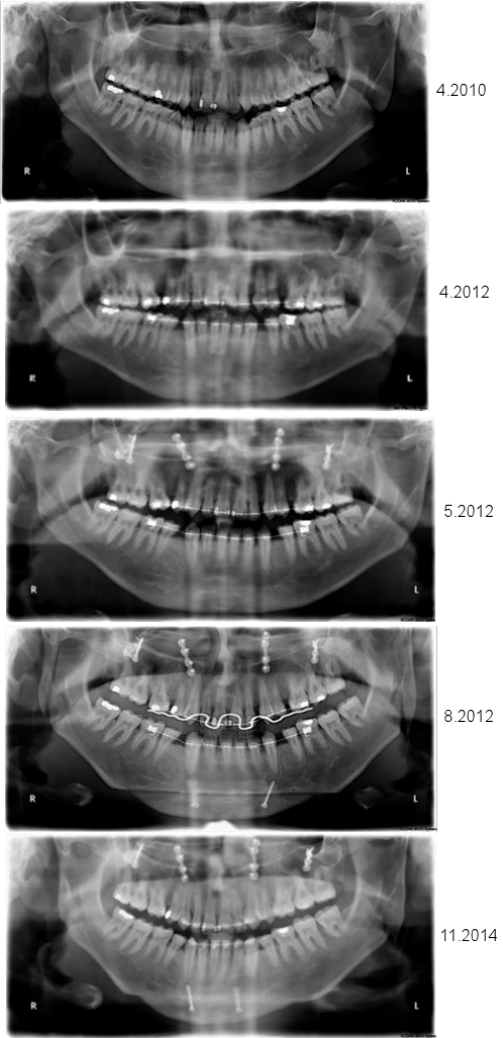

Figure 5: A series of orthopantomograms depicting the patient’s jaw during orthodontic-surgical treatment.

From top to bottom: 1. situation prior to any therapy; 2. after orthodontics; 3. after maxillary osteotomy; 4. after mandibular osteotomies; and 5. after completion of post-surgical orthodontics.